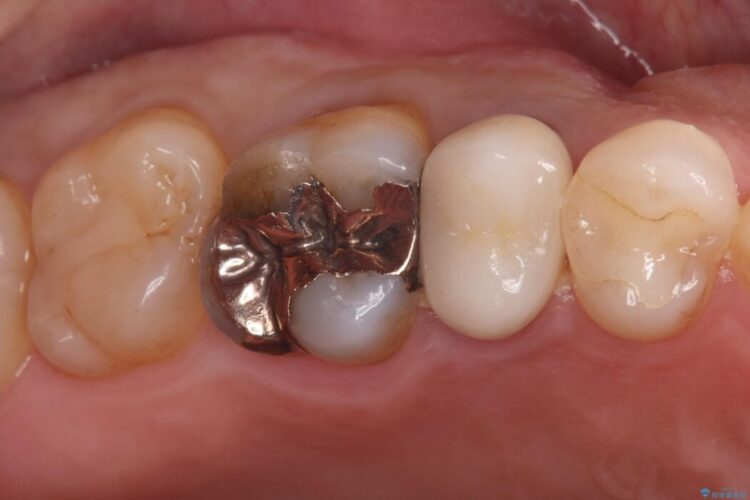

長く使用してきた奥歯の銀歯をやり替えたいとご来院されました。

検査の結果、銀歯の下の歯質が薄くなっており、このままだと割れてしまう(破折)リスクが高い状態でした。

まず、古い銀歯を丁寧に外し、内部に虫歯がないか確認しました。